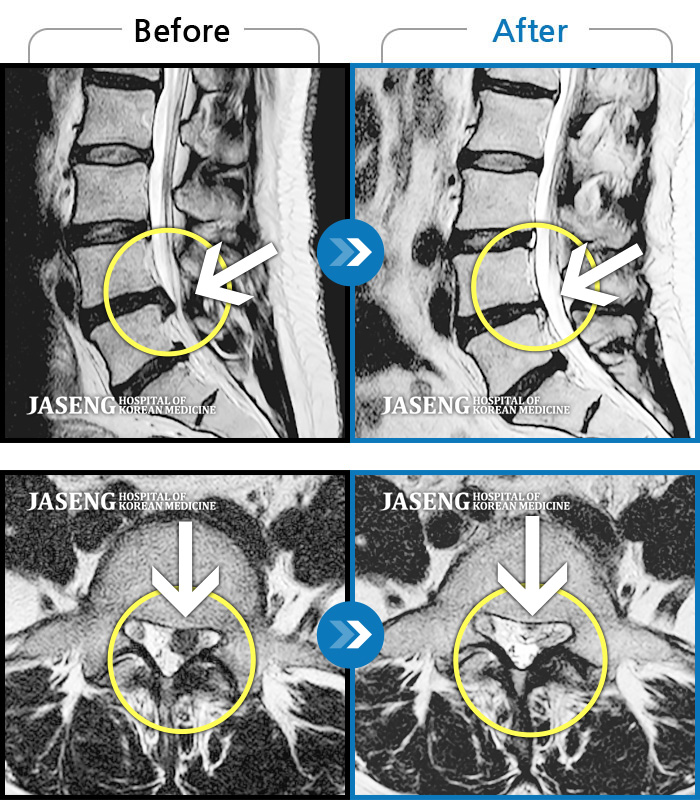

허리디스크

천안 · 김세정 원장

요추 디스크 파열로 극심한 통증을 동반하여 내원하였습니다

촬영시기

2021.12.18 ~ 2024.01.23